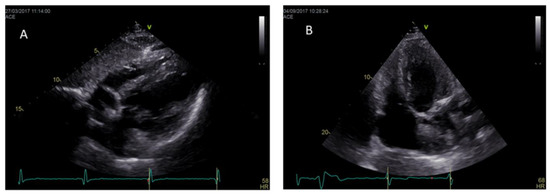

| Cine-sequences | -Measurement of LV mass, ventricular volumes, LV and RV EF, wall motion assessment | -Better quantification of LV papillary muscle mass |